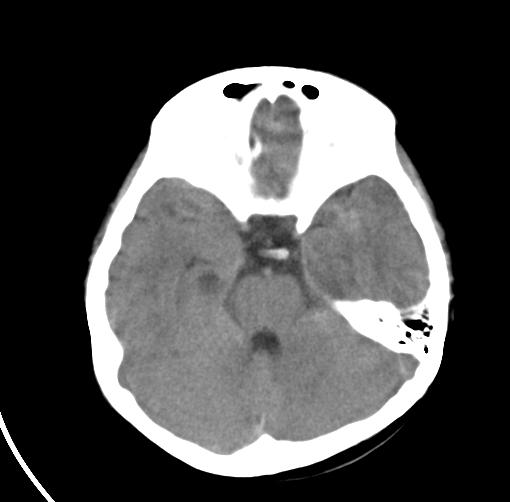

以下是引用sunjh2266在2007-7-31 23:35:00的发言:[br]脉络膜裂,是胚胎发育过程中脉络襞突入侧脑室下角构成脉络丛时形成,位于丘脑下部与海马之间,走行与海马平行。脉络裂内侧通于环池,外侧为侧脑室下角,前面是海马钩及杏仁体,后部与海马沟交通。脉络裂内有参与组成侧脑室脉络丛的脉络膜前动脉及脉络膜后外动脉及其分支走行。[br] mri轴位像,在大脑脚的前外侧多能显示脉络裂的前部,呈左右走行的含脑脊液间隙,前后内外分别与杏仁体、海马、海马钩及侧脑室下角相邻(图1);冠状位像,在扫及脑干的多个层面上,脉络裂均可被清晰显示,因而是显示脉络裂的最佳扫描方式。偏前的部分层面还可见到呈切迹状的海马沟走行于海马旁回内上方;矢状位像,海马旁回上方可见一分叉状裂隙,类似一斜卧的“入”字,接近水平走行的一撇为脉络裂,而由后上向前下走行的一捺为从扣带沟延续而来的海马沟。[br] [br]